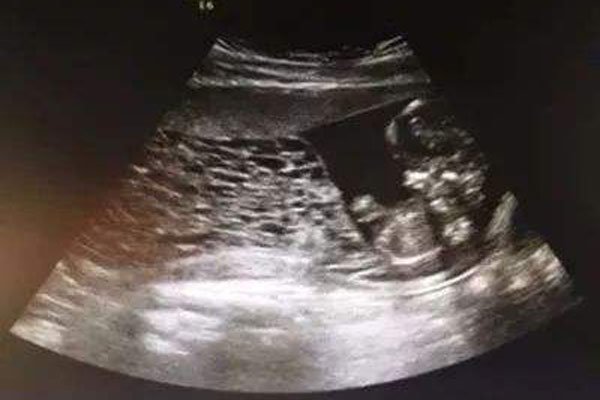

葡萄胎是癌症吗 得了这种病还有没有治愈的可能(2)

葡萄胎是癌症吗 得了这种病还有没有治愈的可能

葡萄胎